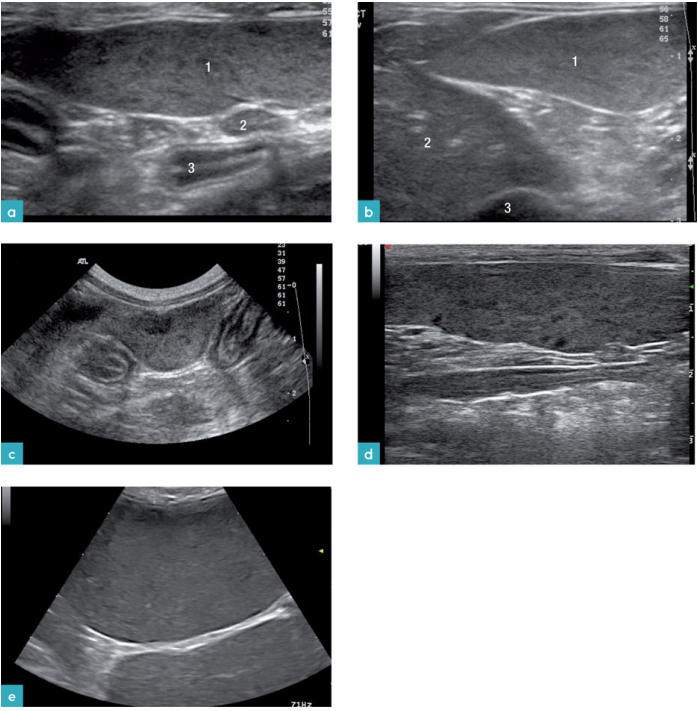

导致猫脾肿大的原因有:髓外造血,慢性贫血,免疫介导性溶血性贫血感染(猫白血病病毒,猫传染性腹膜炎、分支杆菌病,细菌性脾炎,利什曼病等),真菌疾病,如组织胞浆菌病、结节性增生,肿瘤浸润(肥大细胞肿瘤、淋巴瘤、浆细胞瘤),肢端肥大症,嗜酸性粒细胞增多症,血肿,红白血病,骨髓发育不良症候群,骨髓增殖性疾病和血管损伤。有报道称,肝脏疾病引发的静脉淤血会造成脾脏的肿大(图9-15.视频3-7)。

最常见的猫脾脏肿瘤是肥大细胞瘤和淋巴瘤。在一项研究中称,淋巴瘤病例中最常发现的异常就是脾脏肿大。发生肿瘤的脾脏实质有多种回声表现,例如弥散性的低回声点状区域多处小型低回声暗区或独立的低回声团块。在有些病例中,仅发现脾脏实质回声降低但并没有发生脾脏肿大或是仅见独立的脾脏肿块(图9.图3)。同时伴发的症状包括有腹膜腔积液,腹腔淋巴结增大及肝脏病变。

对27只患有脾脏肥大细胞瘤的猫进行研究,观察这些猫的脾脏影像,发现与患有淋巴瘤的病变影像相似。在这些病例中,93%的猫都有不同程度的脾脏肿大,其中有6只猫唯一的异常表现就是脾脏肿大。在2只缺乏典型症状的猫的检查中仅发现有脾脏增大,且有多处高回声的结节。其中1只猫的脾脏呈广泛性高回声,同时伴有脾脏肿大。在其中7只猫的脾脏上发现有单独的结节或肿块(图10.图4)。30%的猫同时伴有肝脏的变化。33%的猫有腹膜腔积液。

患有内脏型肥大细胞瘤的猫,它的副肿瘤综合征表现为胸膜腔和腹膜腔的渗出液中含有嗜酸性粒细胞,同时外周血中也含有较多的嗜酸性粒细胞。然而,这项研究没有发现能够区分肥大细胞瘤和淋巴瘤的超声特征。但是通过这项研究发现,患有淋巴瘤的猫发生腹腔积液的概率比肥大细胞的患猫高(47%比33%),发生肠系膜或腹膜后淋巴结病变概率也比肥大细胞的患猫高(37%比3%)。肥大细胞瘤的患猫脾脏的轮廓则更为不规则,并且高回声病灶仅见于肥大细胞瘤的患猫。这表明小型的高回声结节或弥漫性高回声结节虽是比较少见,但如果发生,可以作为猫脾脏肥大细胞瘤的特异性影像。

在41%的猫髓外造血病例中,伴有或不伴有淋巴样增生,脾脏肿大且回声正常(图12和13)。一部分病例可见,脾脏上有直径0.7-3cm不等的低回声结节或团块。另一些病例可见实质呈低回声,外观呈斑纹状。